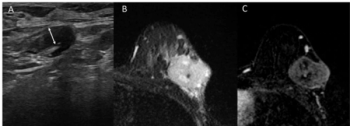

Anterior tumor location was over 14 times more likely to be associated with axillary metastasis after neoadjuvant treatment for breast cancer, according to new breast MRI and ultrasound research.